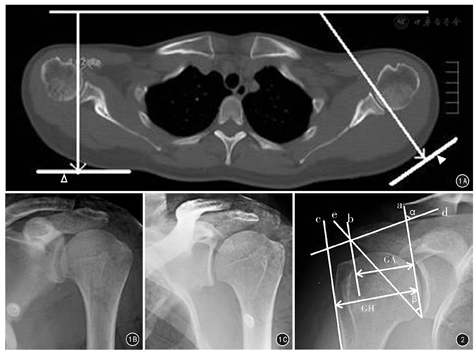

本研究采用标准肩关节真正前后位X线像(standardized true anteroposterior radiograph)[11]。使用德国西门子公司X线机,管电压66.0 kV,管电流10.0 mAs。观察对象在进行拍片时,双臂自然下垂紧贴躯干,五指并拢掌心面向身体正前方。由于肩胛骨平面与人体冠状面呈45°夹角,为使肩胛骨平面与像板平行,拍片时患者需旋转身体直到冠状面与像板呈45°夹角站立。见图1。将采集到的影像资料导入RIS-IMPAX系统,并且保存数据。该系统可提供视野尺寸512×512,像素分辨率0.475 mm。

连接肩胛盂外侧方骨皮质上下边缘作基线(直线a),平行于基线分别作肩峰外侧缘切线(直线b)和肱骨大结节外侧缘的切线(直线c)。肩峰切线到基线的垂直距离(GA)与肱骨大结节切线到基线的垂直距离(GH)之间的比值,称为肩峰指数。(2)肩峰侧倾角的测量方法[8]:于肩峰前方骨皮质的硬化线作平行线(直线d),此线与基线之间的夹角即为肩峰侧倾角(角α)。(3)决定性肩角的测量方法[9]:以直线a为肩峰指数的基线,以肩胛盂外侧缘下端骨皮质与肩峰外侧骨皮质之间做连线(直线e),直线a与直线e的夹角即为决定性肩角(角β)。见图2。同一研究对象的所有参数均在同一张X线像上测量获得,可以直观地观察各参数的变异情况及其内在联系。各数据测量均由笔者进行测量,并进行一致性分析。